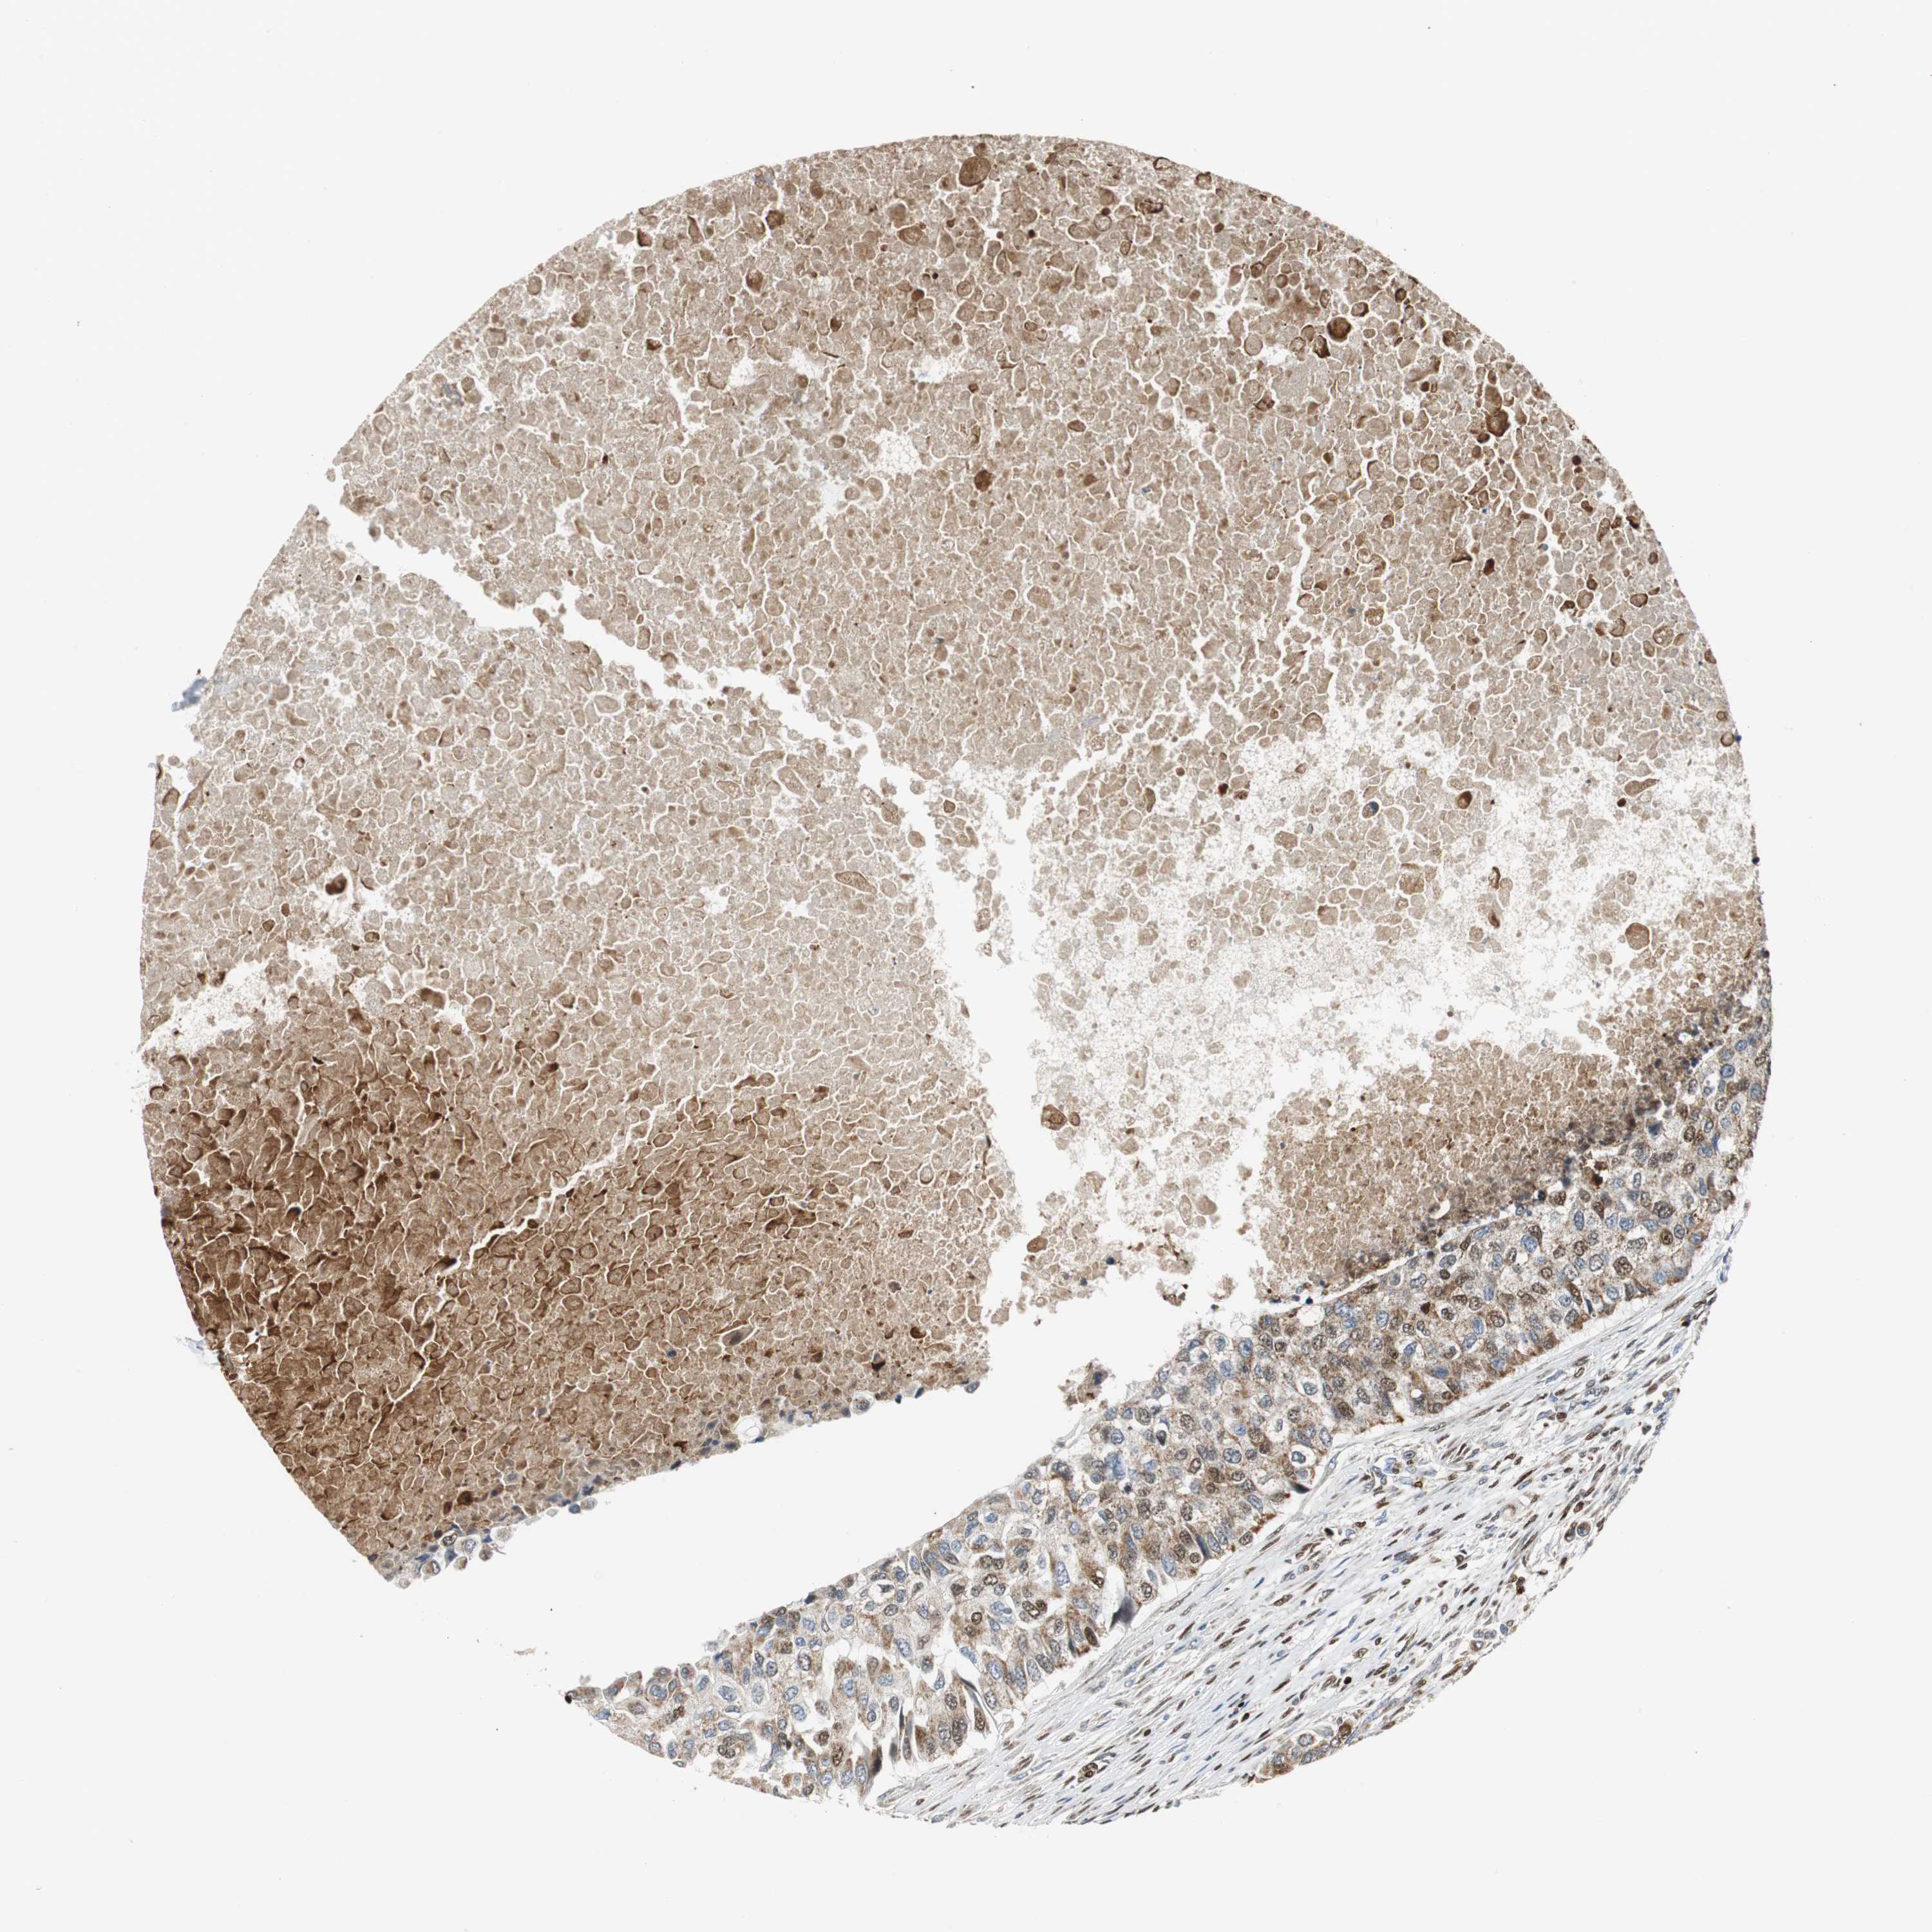

BRCA TCGA BRCA VALIDATION PROTEIN EXPRESSION

ANTIBODIES

AND

VALIDATION